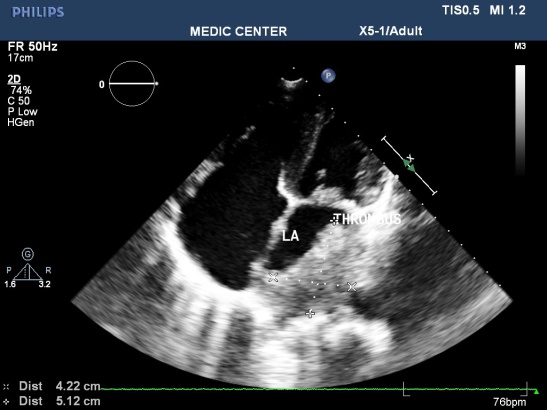

TTE identifies the disease. TEE detects spontaneous contrast and thrombi in LA, LAA of patients with mitral stenosis. It is important to decide using anticoagulation before percutaneous balloon mitral valvuloplasty or surgery (Figures 1-8).

Figure 1. Mitral stenosis with thrombus of LA; “TTE image from Nguyen Tuan Vu”

Rheumatic valvular diseases: Mitral stenosis is majority, stroke often occurs in mitral stenosis patients with atrial fibrillation, LA enlargement, spontaneous contrast, absence or presence of thrombus.